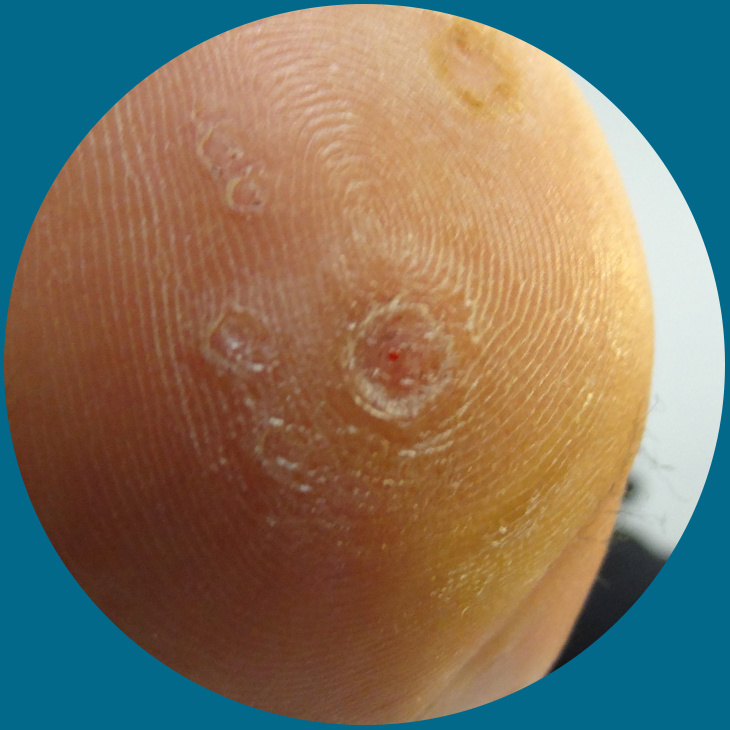

Verrucae are a common complaint amongst children and adults. A verruca is a small skin lesion which is commonly found on the bottom surface of the foot. The lesion is usually approximately 1cm in diameter but can be larger.

- All verrucae are caused by the human papilloma virus. This is common in all environments but does not readily attack the skin.

- If there is a break, scratch or a thorn in the skin, this will give the virus a opportunity to enter the skin.

- Verrucae are commonly contracted in communal places such as swimming pools, showers and changing areas. This is why children are more at risk of contracting verrucaes in school changing rooms and swimming pools.

- Excessive moisture or excessive dryness of the skin can lead to small crack in the skin which allows the virus to enter the skin.

Verrucae are a common complaint amongst children and adults. A verruca is a small skin lesion which is commonly found on the bottom surface of the foot. The lesion is usually approximately 1cm in diameter but can be larger.

- All verrucae are caused by the human papilloma virus. This is common in all environments but does not readily attack the skin.

- If there is a break, scratch or a thorn in the skin, this will give the virus a opportunity to enter the skin.

- Verrucae are commonly contracted in communal places such as swimming pools, showers and changing areas. This is why children are more at risk of contracting verrucaes in school changing rooms and swimming pools.

- Excessive moisture or excessive dryness of the skin can lead to small crack in the skin which allows the virus to enter the skin.